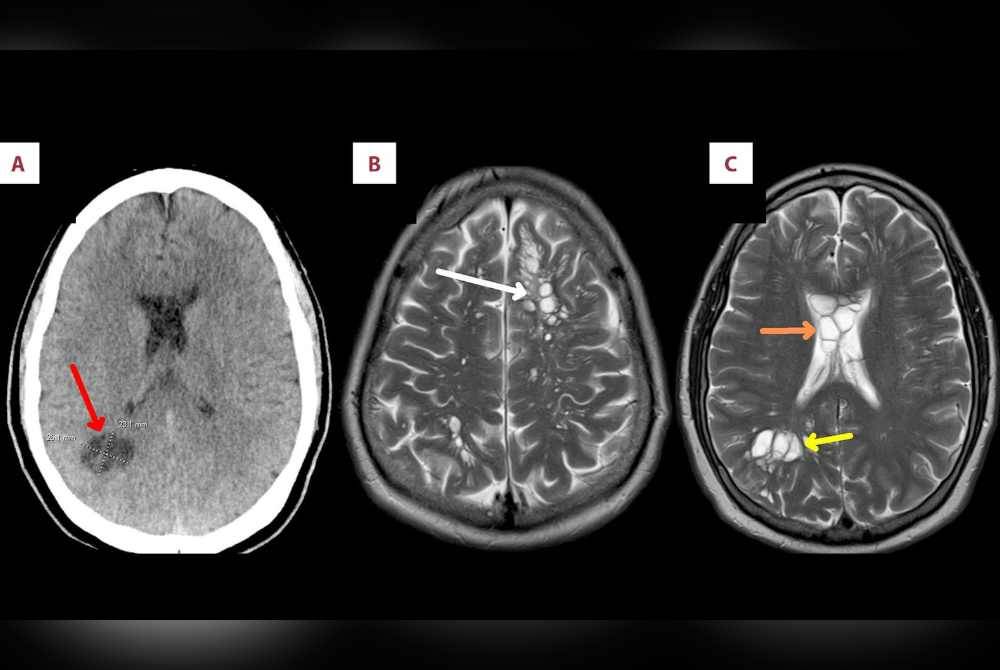

Doktor yang melakukan imbasan mendapati sejumlah telur cacing pita 'bersarang' dalam otaknya.

Selepas membuat pemeriksaan lanjut, lelaki itu disahkan menghidap penyakit neurocysticercosis, sejenis jangkitan daripada larva cacing pita babi yang boleh memasuki tisu seperti otak dan otot.